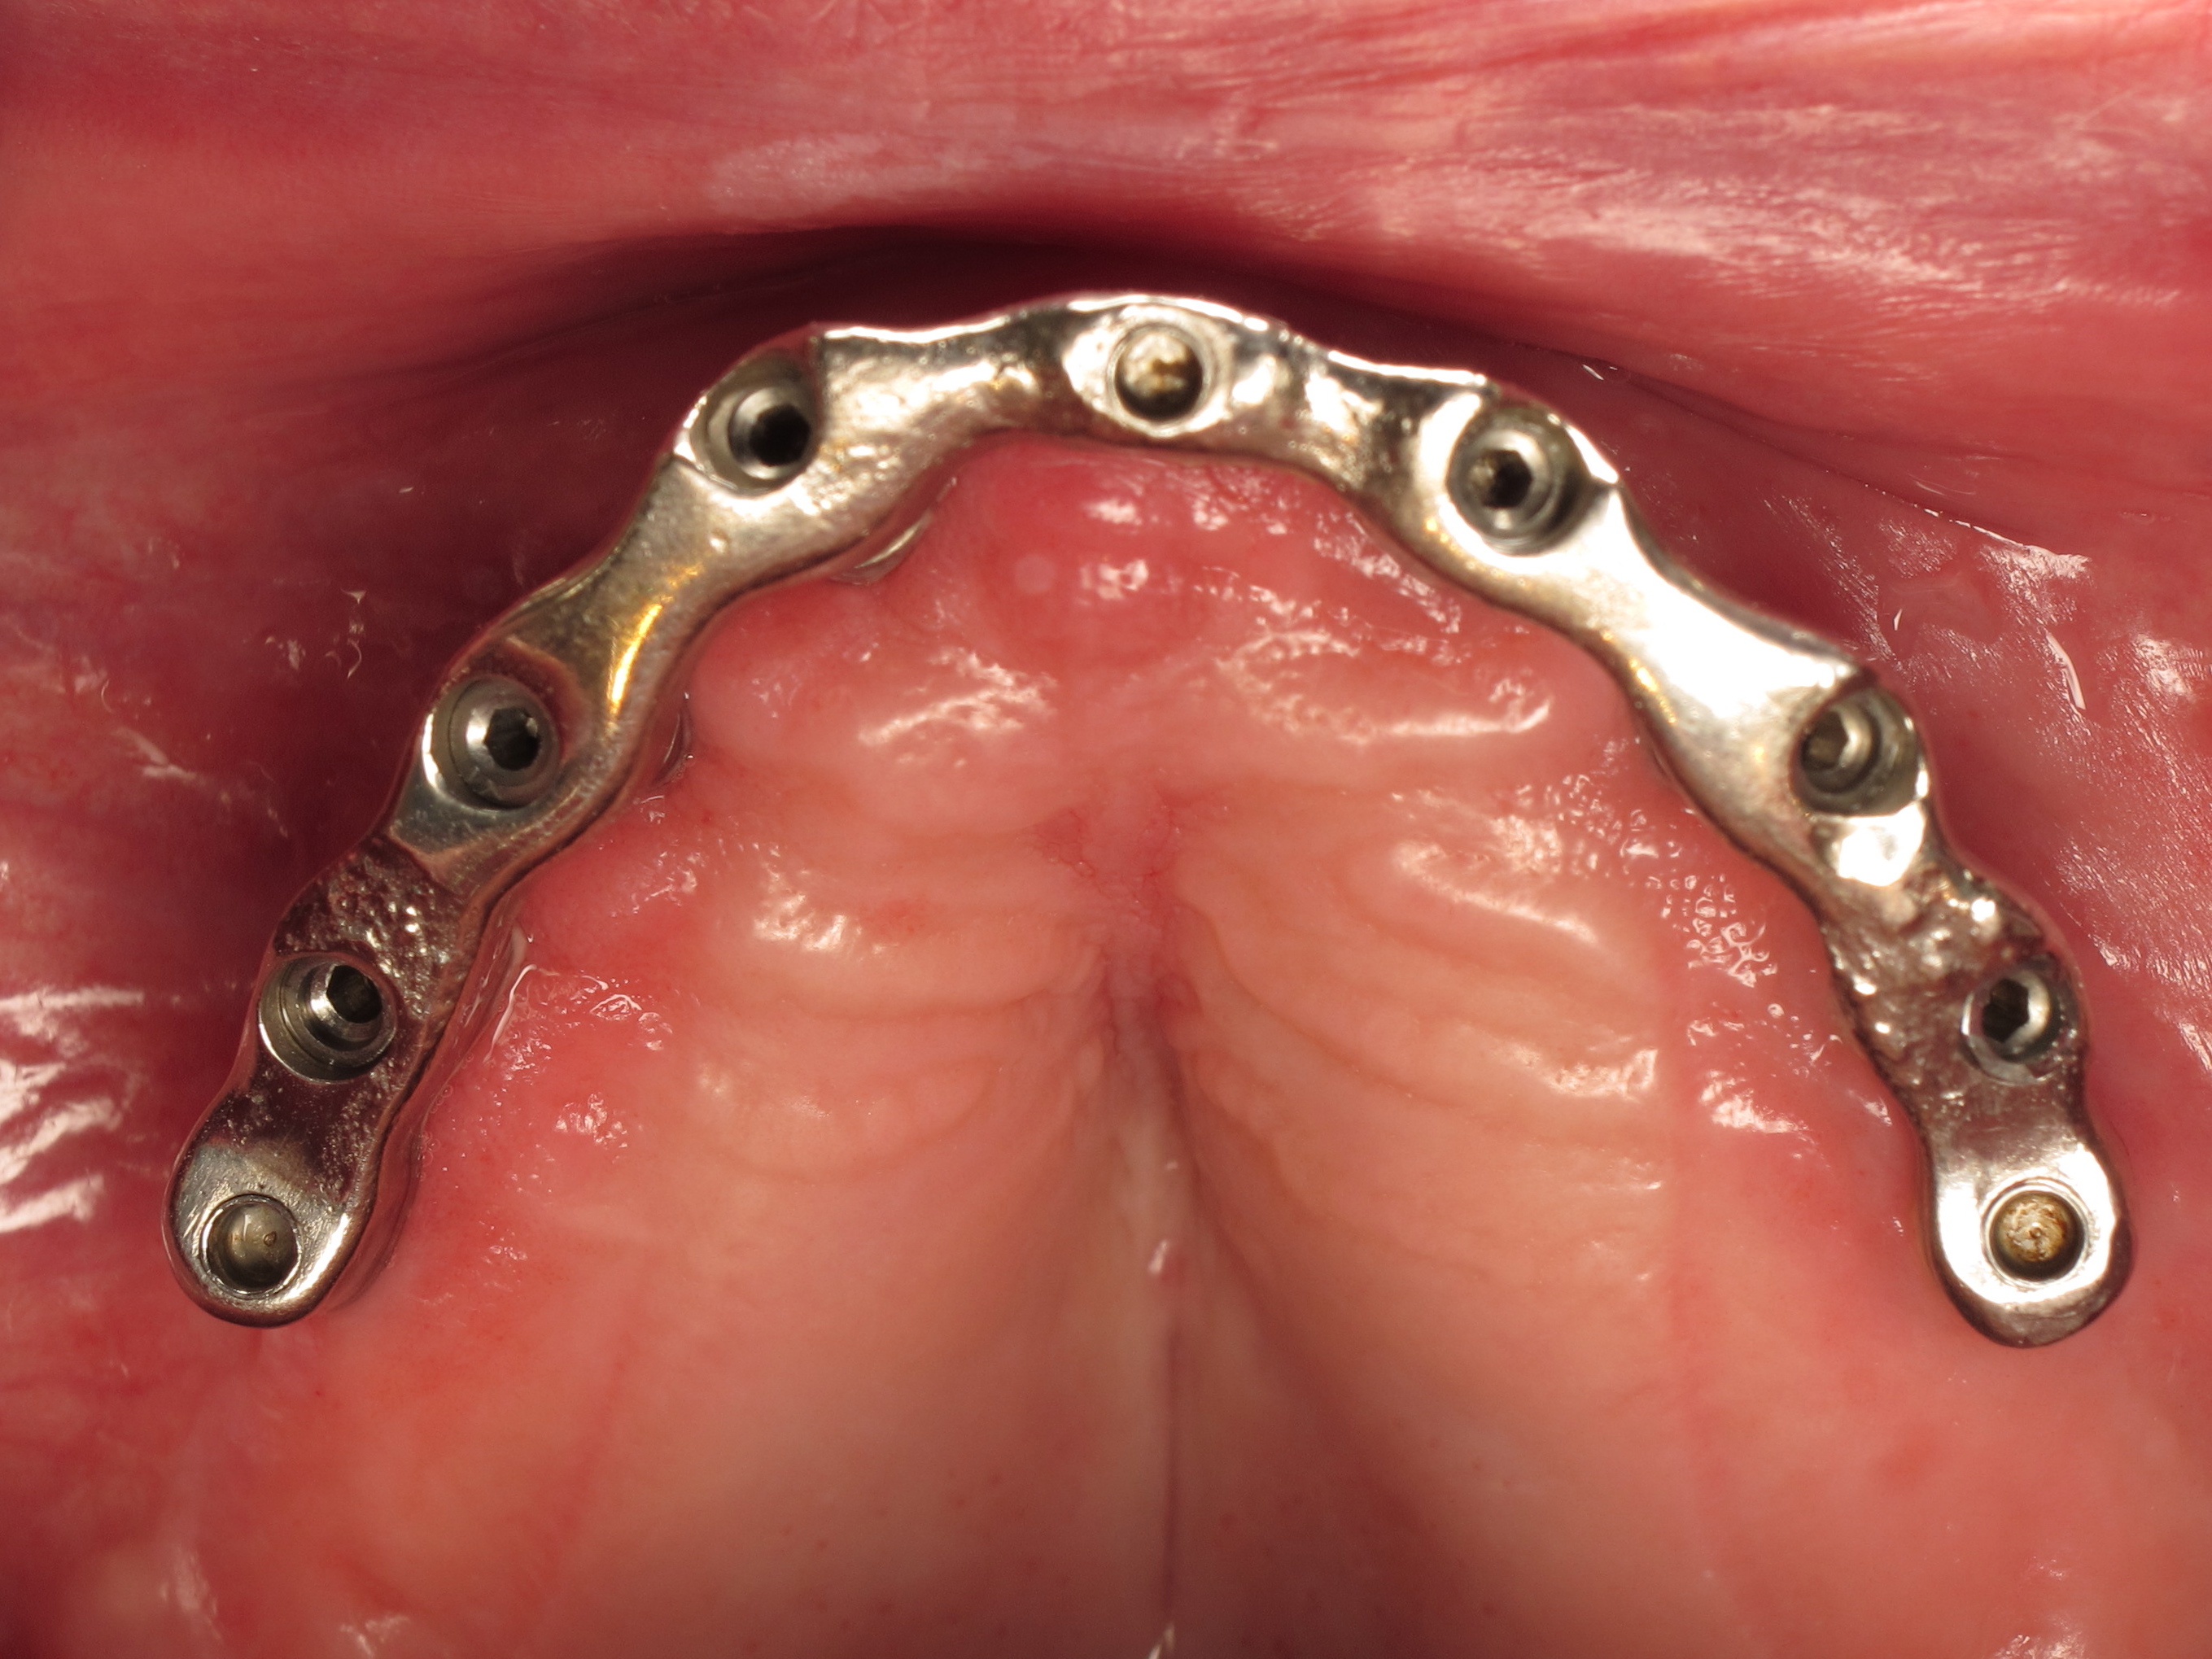

Il est par ailleurs important dans le cas d’une barre réduite au secteur antérieur de conserver un appui palatin de la prothèse afin d’avoir une sustentation verticale plus efficace et de diminuer les stress mécaniques sur la barre antérieure en cas de pressions importantes au niveau des molaires (photo de gauche).

Si la barre est étendue sur toute l’arcade (photo de droite) le palais pourra alors être supprimé car la prothèse sera totalement implanto-portée.

- barre sur 6 implants (à 20 ans)